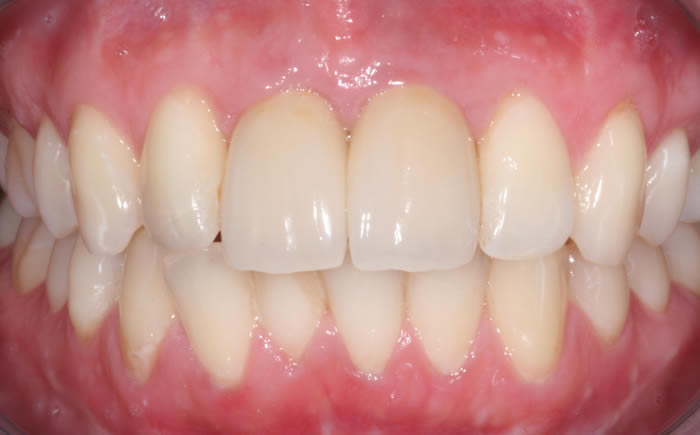

Case Two (8 images)

Full set of lower teeth fixed onto five dental implants.